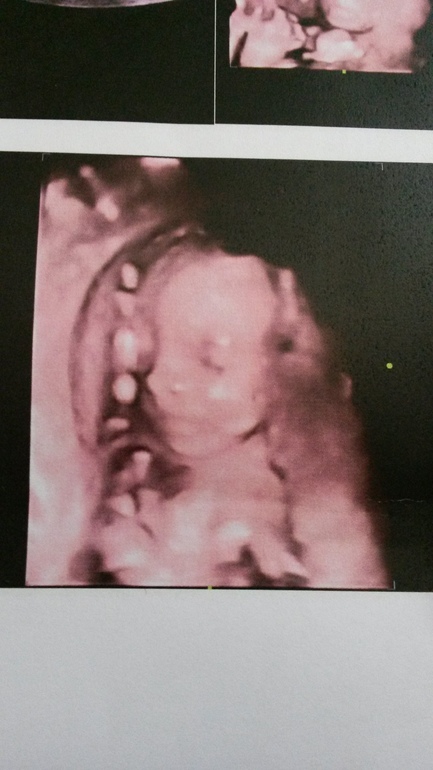

Это фото твой малышки? Какая же она прелесть, совсем чкоро ты с ней встретишься.

ага,доча моя)),как смотрю на нее сразу настроение поднимается,таак на меня похожа,хоть что то моё)),а то в папу должна быть черненькая-восточная кровь.